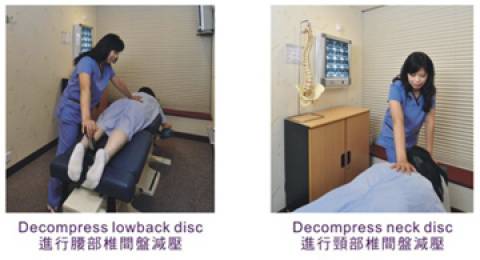

Cox®軟骨減壓治療法-不倚靠止痛藥鎮痛,矯正脊椎

脊醫會利用冰敷、電波療法、Cox®治療法及手療法來令突出的 軟骨復位及幫助病人鬆弛肌肉和減輕痛楚。治療期一般會比其它病症為長,大約 2-3 個月,視乎病人的嚴重程度而定。

匯萃醫療集團採用“Cox®椎間盤(軟骨)減壓治療法(Cox®Decompression Manipulation) ”,Cox®軟骨減壓治療法是由美國的Dr. James M. Cox於1960年發明。他使用了“牽引” 和“減壓” 兩種不同的技術來操控脊椎的移動。本診所創辦人王鳳恩為香港首名持有Cox®軟骨減壓治療證書的註冊脊醫,並把最先進治療脊骨神經的技術帶到香港。

Cox®軟骨減壓治療特別有效地減輕腰背痛、腳痛及頸肩痛的症狀,對椎間盤(軟骨) 突出、坐骨神經痛、脊椎狹窄症、脊椎滑脫症等脊科問題引發的痛症尤其顯著。